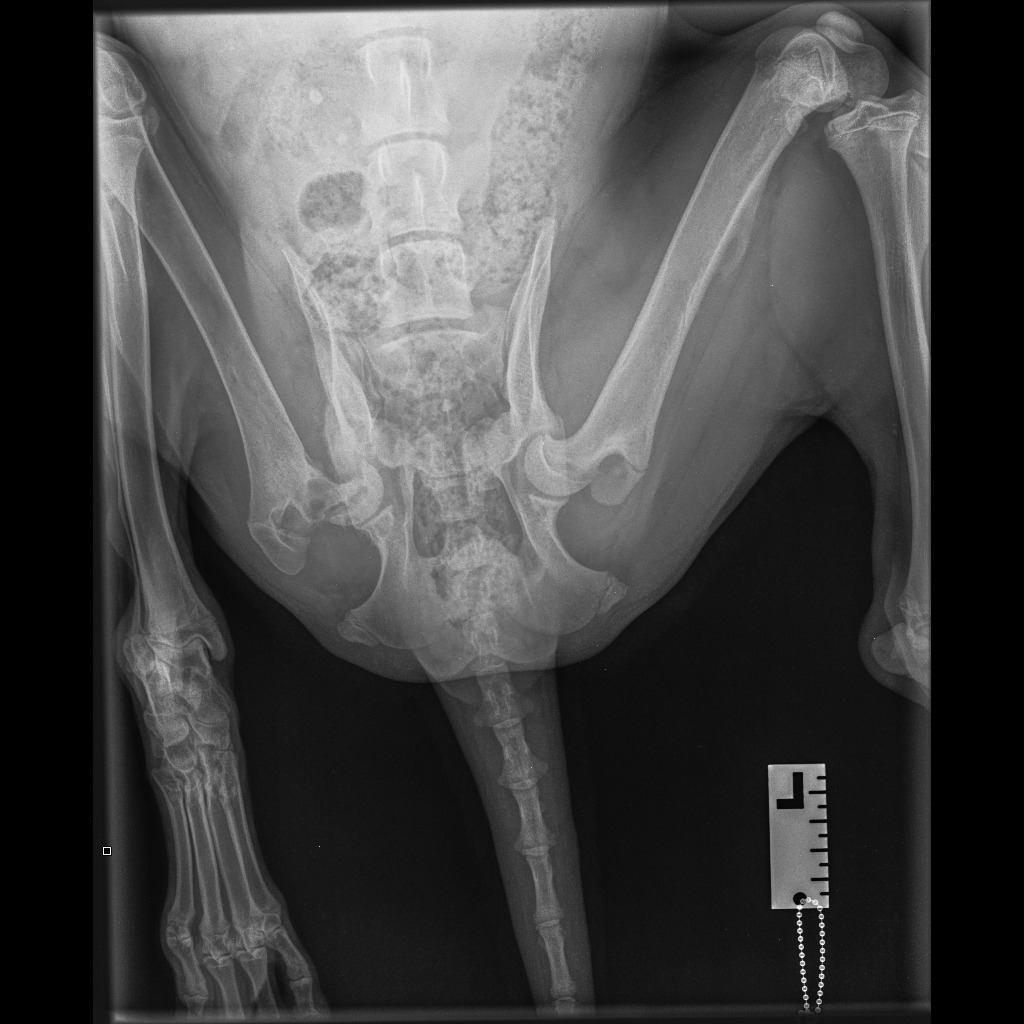

The surgery will only go ahead with a 50% deposit paid on the morning of the procedure, with the remaining balance due at discharge. Biggie is in severe, unmanageable pain, and the vet’s assessment is that the only remaining options to this surgery is immediate euthanasia – or a total hip replacement that is four times more expensive. Attached are the surgery estimate (to be paid), pre-evaluation and medication costs (already paid), and X-ray images.